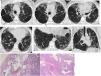

Más datosLa exposición al tabaco guarda una relación reconocida con el desarrollo de enfermedades de la vía aérea y el parénquima pulmonar. Aparte de la enfermedad pulmonar obstructiva crónica, en algunos individuos el humo del tabaco puede desencadenar mecanismos de daño intersticial que resultan en variadas alteraciones patológicas y fibrosis pulmonar. Se ha reconocido un grupo de entidades con una relación causal establecida con el tabaco, que incluye la bronquiolitis respiratoria con enfermedad pulmonar intersticial, la neumonía intersticial descamativa, la histiocitosis de células de Langerhans y la neumonía eosinófila aguda. Aunque el tabaco se considera factor de riesgo, aún es ambiguo su papel e impacto en el desarrollo de la fibrosis pulmonar idiopática, la entidad clínica diferenciada que se ha denominado combinación fibrosis pulmonar y enfisema, y la neumonía intersticial no específica. La definición de la fibrosis intersticial asociada al tabaco es relativamente reciente, con características histológicas diferenciadas. La interconexión probable entre los mecanismos que determinan la inflamación y la fibrosis pulmonar en todos estos procesos referidos se traduce con frecuencia en una superposición de rasgos histológicos, clínicos y radiológicos en el mismo paciente, que en algunos casos puede determinar patrones radiológicos de neumopatía intersticial no clasificables. Por ello es recomendable un abordaje combinado para el diagnóstico, que debe estar basado en la interpretación conjunta de las características histológicas y los hallazgos radiológicos, en el contexto clínico apropiado. Nuestro objetivo se centra en la descripción de los hallazgos radiológicos en la tomografía computarizada de alta resolución, en correlación con las manifestaciones clínicas y las alteraciones histológicas subyacentes al patrón radiológico.

Exposure to smoke is associated with the development of diseases of the airways and lung parenchyma. Apart from chronic obstructive pulmonary disease (COPD), in some individuals, tobacco smoke can also trigger mechanisms of interstitial damage that result in various pathological changes and pulmonary fibrosis. A causal relation has been established between tobacco smoke and a group of entities that includes respiratory bronchiolitis-associated interstitial lung disease (RB-ILD), desquamative interstitial pneumonia (DIP), Langerhans cell histiocytosis (LCH), and acute eosinophilic pneumonia (AEP). Smoking is considered a risk factor for idiopathic pulmonary fibrosis (IPF); however, the role and impact of smoking in the development of this differentiated clinical entity, which has also been called combined pulmonary fibrosis and emphysema (CPFE) as well as nonspecific interstitial pneumonia (NIP), remains to be determined. The definition of smoking-related interstitial fibrosis (SRIF) is relatively recent, with differentiated histological characteristics. The likely interconnection between the mechanisms involved in inflammation and pulmonary fibrosis in all these processes often results in an overlapping of clinical, radiological, and histological features in the same patient that can sometimes lead to radiological patterns of interstitial lung disease that are impossible to classify. For this reason, a combined approach to diagnosis is recommendable. This combined approach should be based on the joint interpretation of the histological and radiological findings while taking the clinical context into consideration. This paper aims to describe the high-resolution computed tomography (HRCT) findings in this group of disease entities in correlation with the clinical manifestations and histological changes underlying the radiological pattern.